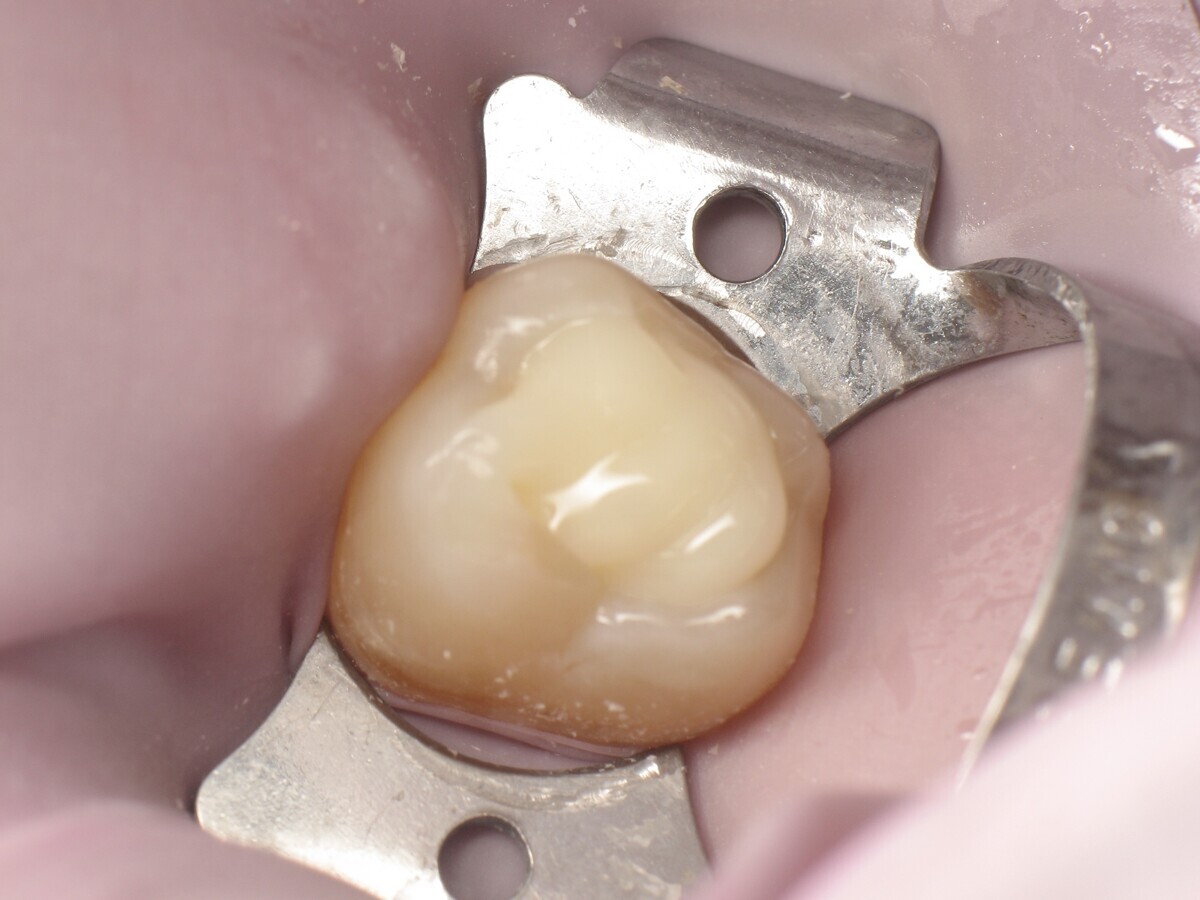

La secuencia fotográfica muestra la cavidad después de la aplicación y fotopolimerización del adhesivo y el modelado que se obtiene con el composite termoviscoso. Fotos: Yassine HARICHANE

Este artículo describe el tratamiento de una cavidad clase I en un molar utilizando un composite termoviscoso mediante la técnica de la almohadilla (Figura 1). En primer lugar, se registran los detalles anatómicos utilizando una resina transparente, fluida y fotopolimerizable (Clip Flow, VOCO). El diente se aísla con un dique antes de aplicar el composite transparente a la superficie oclusal con un cepillo aplicador y fotopolimerizar durante 10 segundos (Figuras 2-4). La almohadilla oclusal así obtenida (Figura 5) debe almacenarse en alcohol (etanol o isopropanol) para eliminar la capa de inhibición. Luego se limpia la cavidad clase I (Figuras 6 y 7). A continuación se graba el esmalte durante 30 segundos y la dentina durante 15 segundos (Conditioner 36, Dentsply Sirona) y luego se enjuaga bien (Figuras 8 a 10). Debido al bajo espesor de la dentina remanente, también se aplica protección pulpar (Telio Desensitizer, Ivoclar Vivadent) (Figura 11). Luego se frota el adhesivo sobre las superficies dentales durante 20 segundos (Futurabond DC, VOCO), luego se seca bajo una pulverización de aire sin aceite graso durante 5 segundos y luego se fotopolimeriza durante 10 segundos (Figuras 12, 13). Para una humectación óptima, el fondo de la cavidad se cubre con un compuesto fluido de baja viscosidad (GrandioSO Light Flow, A3.5, VOCO) y se fotopolimeriza durante 20 segundos (Figuras 14, 15). Utilizando el Dispensador VisCalor, un dispensador portátil que permite el calentamiento y la aplicación simultánea de resinas, la cavidad se llena luego con un composite termoviscoso bulk (VisCalor Bulk, A2, VOCO).

El composite calentado tiene una consistencia fluida para un perfecto manejo y se puede aplicar en capas de hasta 4 mm (Figura 16). A medida que se enfría hasta la temperatura corporal, la viscosidad del composite termoviscoso aumenta, lo que lo hace muy fácil de modelar (Figura 17). Finalmente, se realiza la fotopolimerización durante 20 segundos (potencia ≥ 1.000 mW/cm2, Figura 18). El uso de un composite bulk permite un llenado rápido en un solo paso. Si se requiere una segunda capa, la capa superior también se puede realizar con composite termoviscoso estético universal VisCalor en color A1 (VisCalor, VOCO, Figura 19), que se fotopolimeriza en incrementos de 2 mm. La consistencia innovadora del composite termoviscoso permite una reproducción fácil de la anatomía y una eliminación fácil del exceso de material (Figura 20) [Ilie et al. 2014]. A continuación se aplica la almohadilla oclusal creada previamente (Figura 21). La fotopolimerización se realiza primero con la almohadilla y luego sin durante 20 segundos cada una (Figuras 22 a 24). No se requiere material separador entre el material compuesto y la almohadilla. Debido a la eliminación previa de la capa de inhibición de la almohadilla, hay muy pocos o ningún punto de contacto, de modo que no se puede crear ningún enlace químico real entre la almohadilla y la resina. Los pocos puntos de contacto presentes solo significan que puede sentir una ligera resistencia cuando se retira la almohadilla después del primer ciclo de fotopolimerización.

Figura 17. Modelado de VisCalor Bulk.

Figura 20. Eliminación de excesos.